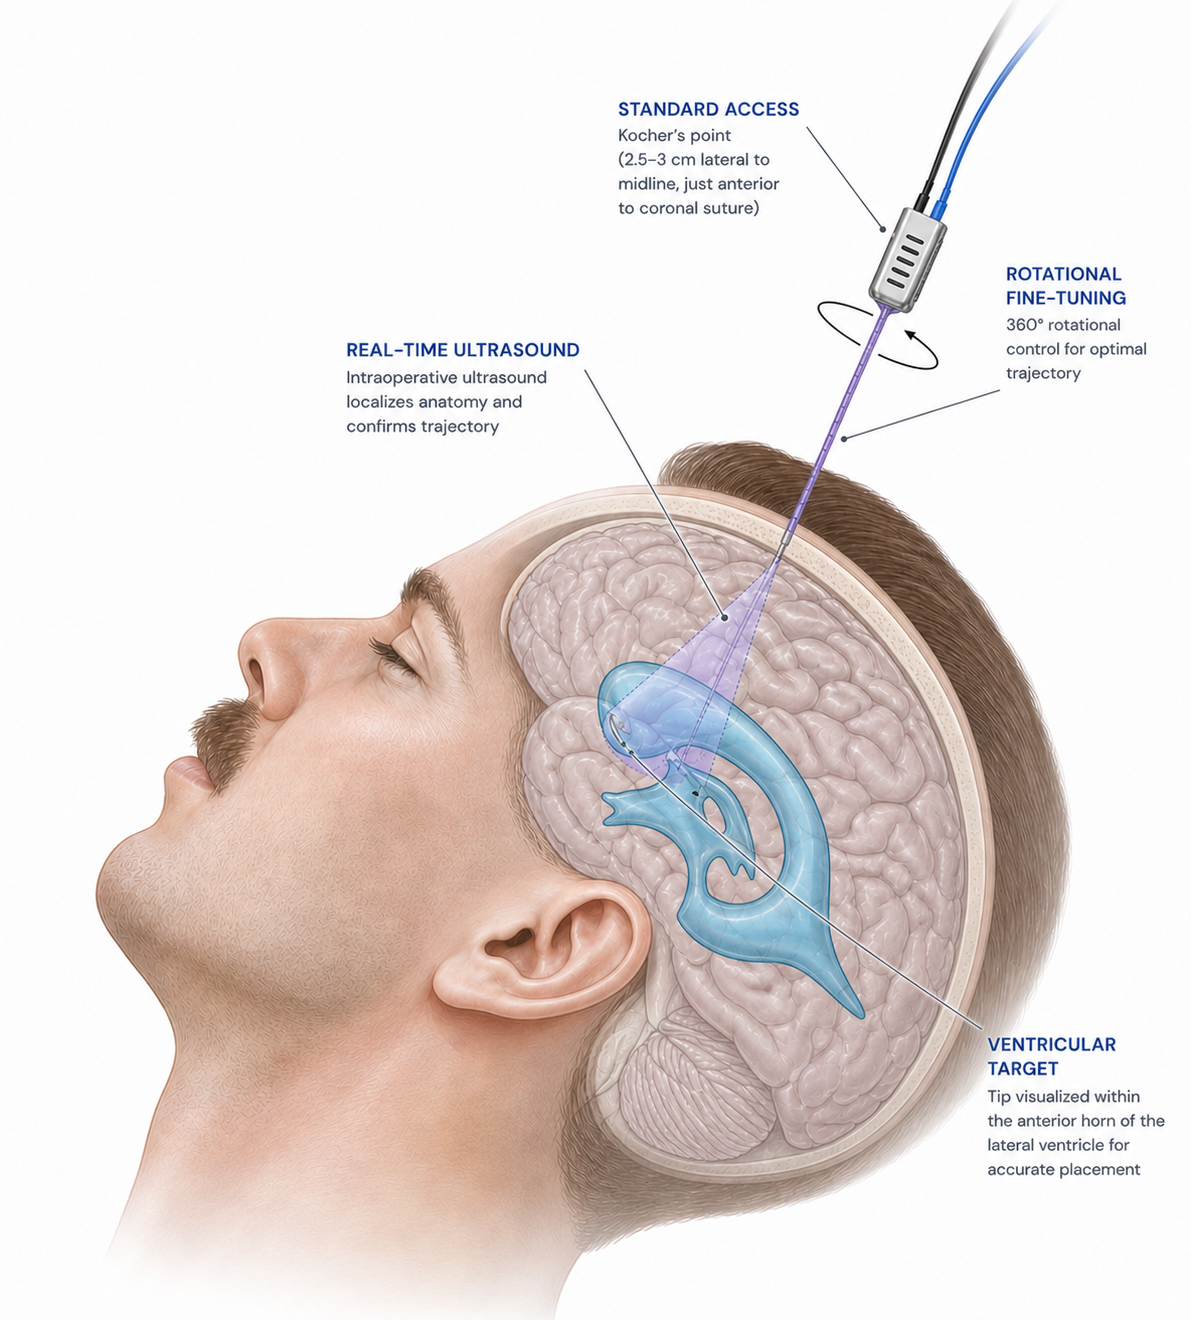

A new approach to EVD placement

Our team is building the world’s first ultrasound and reconstruction algorithm capable of 3D imaging from an astounding 1.65mm diameter transducer. This provides neurosurgeons the tools they need for successful EVD placement in even the most challenging situations.

Three integrated technologies designed to make ventricular access visible in real time

Due to the life-threatening nature of rapid brain swelling after traumatic brain injury (TBI), neurosurgeons will place EVDs to remove Cerebral Spinal Fluid (CSF) to prevent brain herniation, permanent disability, and death, which may happen in a matter of hours, if not done promptly.

Seeing Blind

With this urgency, placement of EVDs are often done at the bedside (outside of the operating room) based on external anatomy alone (“blind approach”). Neurosurgeons have no way to see inside the skull to place EVDs in their target location (anterior horns of lateral ventricles).